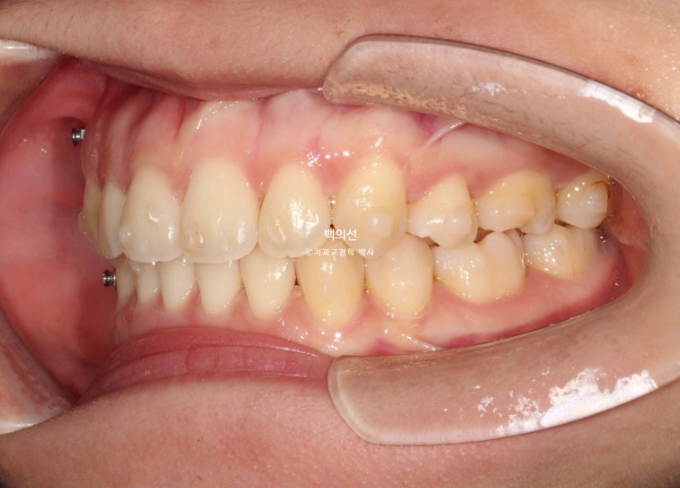

23.01~25.07

어금니 교합이 기존 3급에서 정1급 교합관계로 바뀌었습니다.